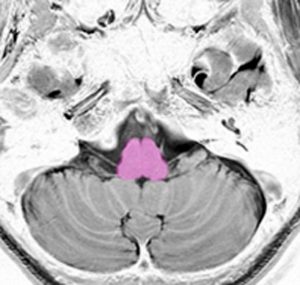

これは脳の中心部を縦切りにした写真です。脳幹部は上から順に,中脳 midbrain (黄色),橋 pons(オレンジ),延髄 medulla oblongata(ピンク)と呼ばれます。